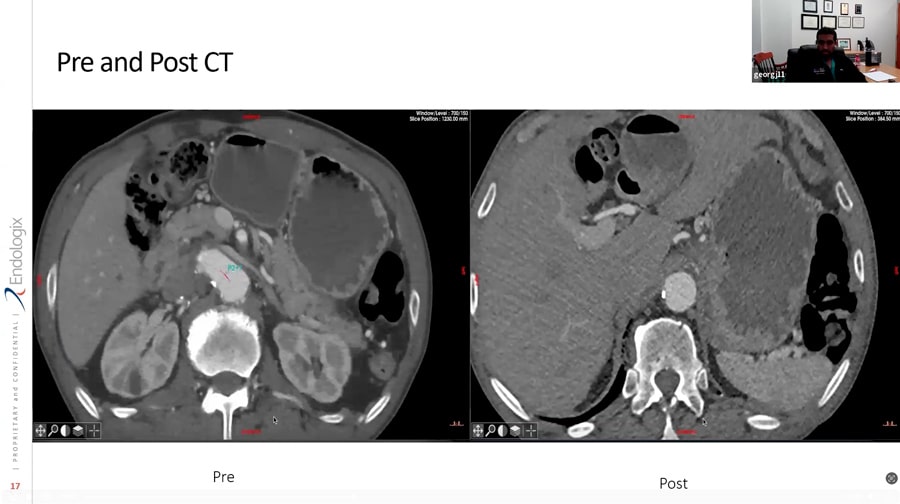

AFX2 Pre/Post Case Images

EVAR Solutions using ALTO - Drs. Justin George and Jarrad Rowse Webinar

ALTO - Drs Justin George and Jarrad Rowse